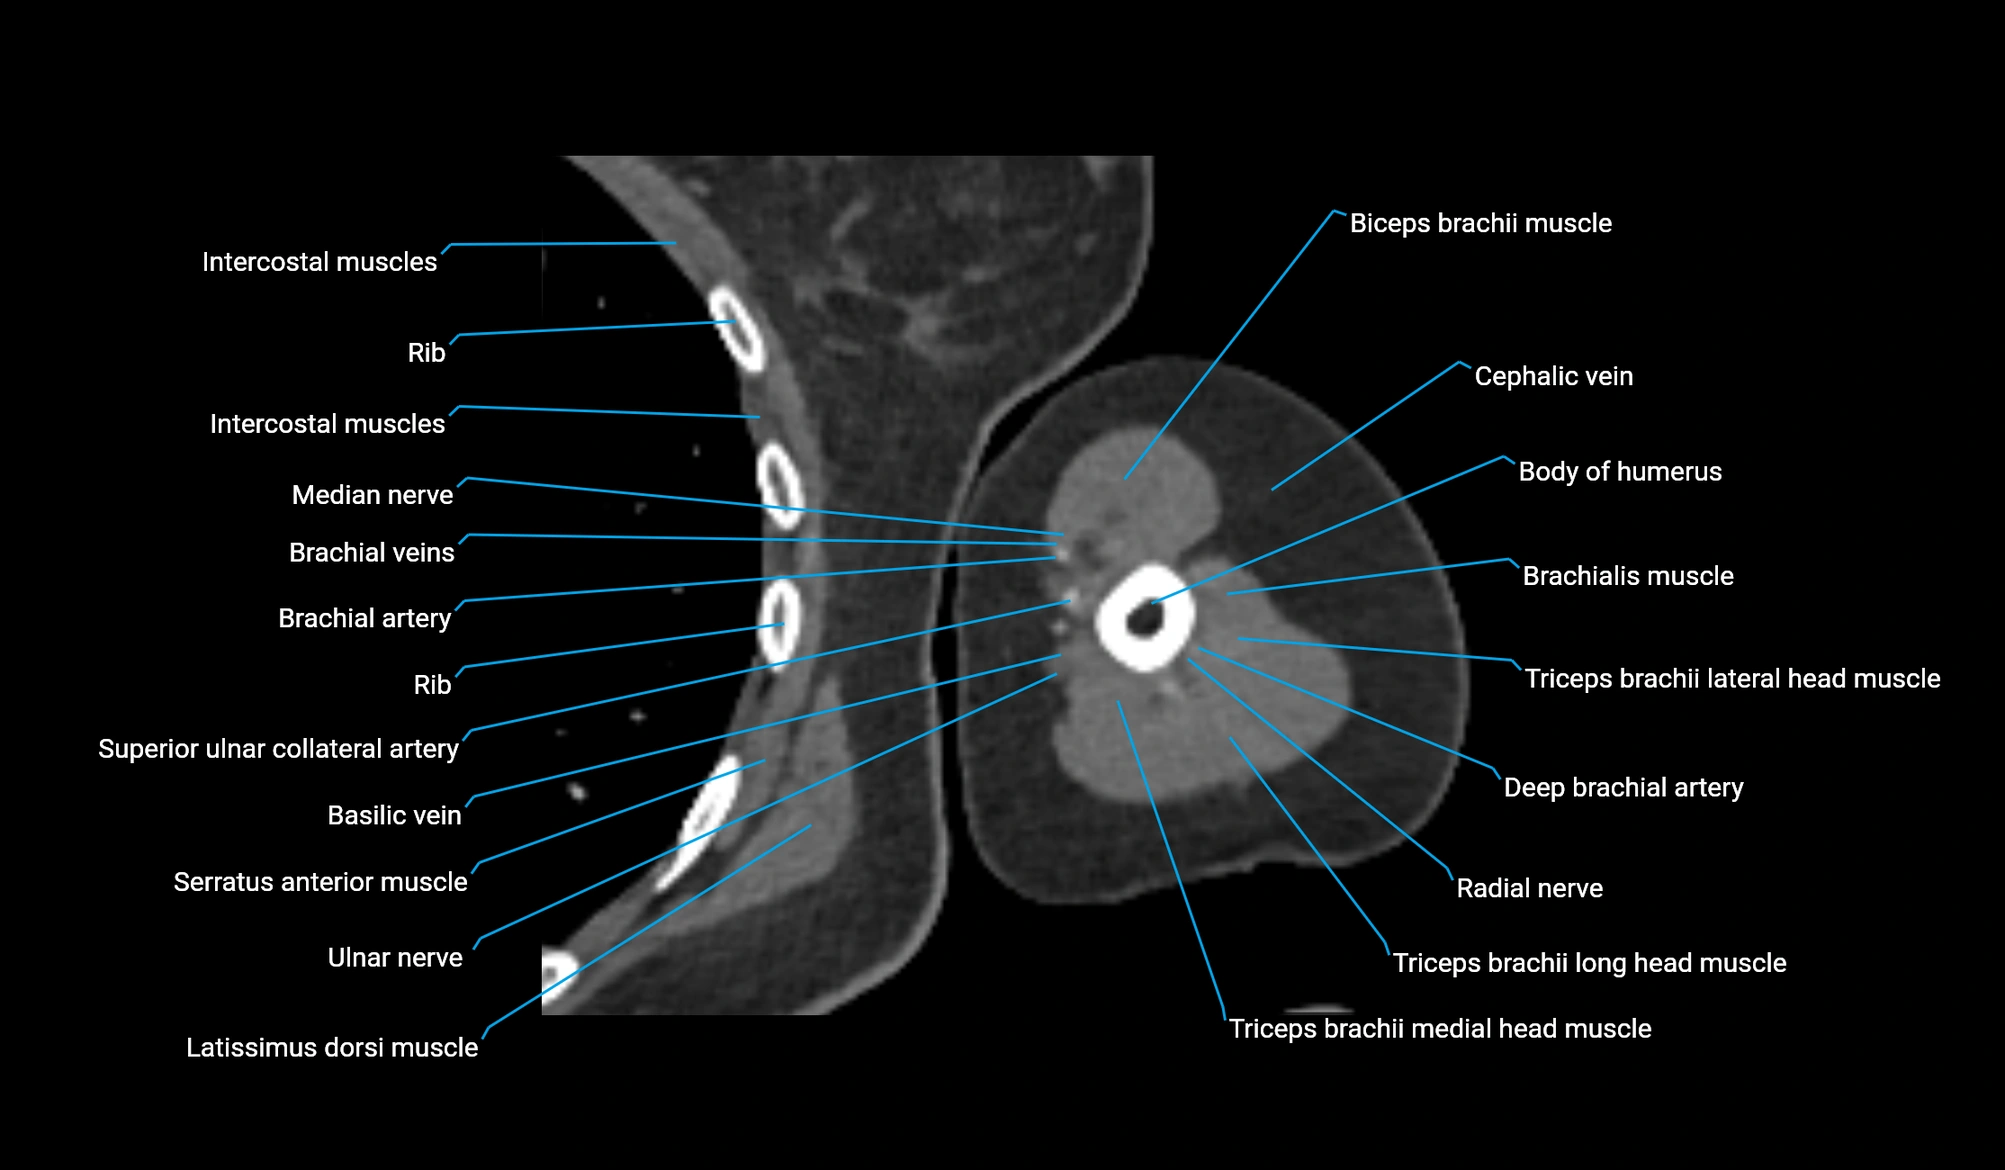

- Body of humerus

- Brachial artery

- Brachialis muscle

- Cephalic vein

- Deep brachial artery

- Lateral head of triceps brachii muscle

- Long head of triceps brachii muscle

- Medial head of triceps brachii muscle

- Median nerve

- Radial nerve

- Superior ulnar collateral artery

- Ulnar nerve

- Basilic vein

- Biceps brachii muscle